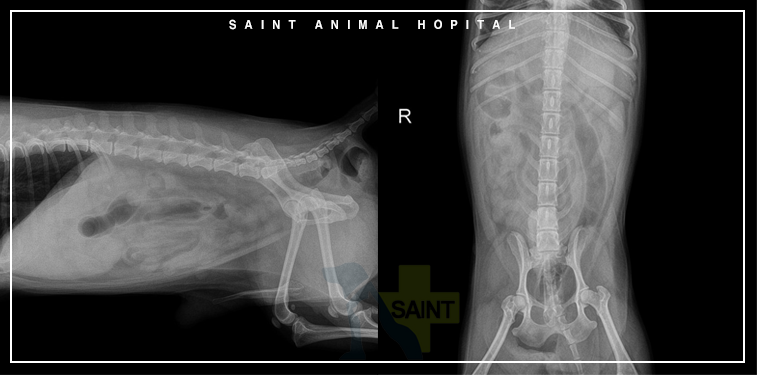

하지만 엉덩이 부위가 비정상적으로 튀어나온 것을 확인할 수 있었습니다만, 이렇게 된 것은 몇 년 정도였다고 합니다.학부모님과 상담 후 영상검사도 함께 진행하였습니다.

초음파와 방사선 검사에서 탈장이 확인됐지만 특정 조직에 대한 판단은 어려웠습니다.직장 회음부 탈장이 가장 의심스러웠어요.꿈*이 나이가 많아서 학부모님과 충분한 상담 후 수술을 진행하기로 결정하였습니다.